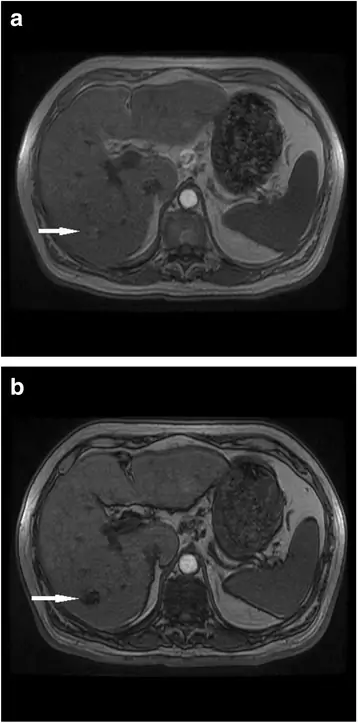

Поскольку многие пациенты с ГЦК не соответствуют критериям трансплантации или хирургического вмешательства, значительная часть пациентов получает местно-регионарную или системную терапию, и поэтому им требуется визуализация после терапии для оценки первоначального ответа и рецидивирующего заболевания. Не существует установленных руководящих принципов для идеальных интервалов времени наблюдения. Рецидив в 6, 5 раз чаще встречается в первый год после терапии, чем во второй год, поэтому в большинстве руководств рекомендуется 3-месячная интервальная визуализация в первый год после лечения (58). Мы проводим визуализацию с 3-месячными интервалами в течение одного года с последующими 6-месячными интервалами в течение 2 лет, а затем возвращаемся к ультразвуковому скринингу. Важно использовать одну и ту же методику для каждого последующего наблюдения, поскольку сравнение КТ и МРТ может быть сложной задачей. Мы обычно используем МРТ для наблюдения, поскольку результаты визуализации могут быть более трудными для интерпретации после лечения, и изображения вычитания могут быть действительно полезными (Рис. 4).

figure4

66-летняя женщина с циррозом гепатита С после микроволновой абляции ГЦК. Предварительно контрастное изображение после микроволновой абляции (a) показывает полость с высоким собственным сигналом при взвешенной визуализации T1. Изображение вычитания (b) удаляет высокий сигнал, что не приводит к улучшению

Изображение в полном размере